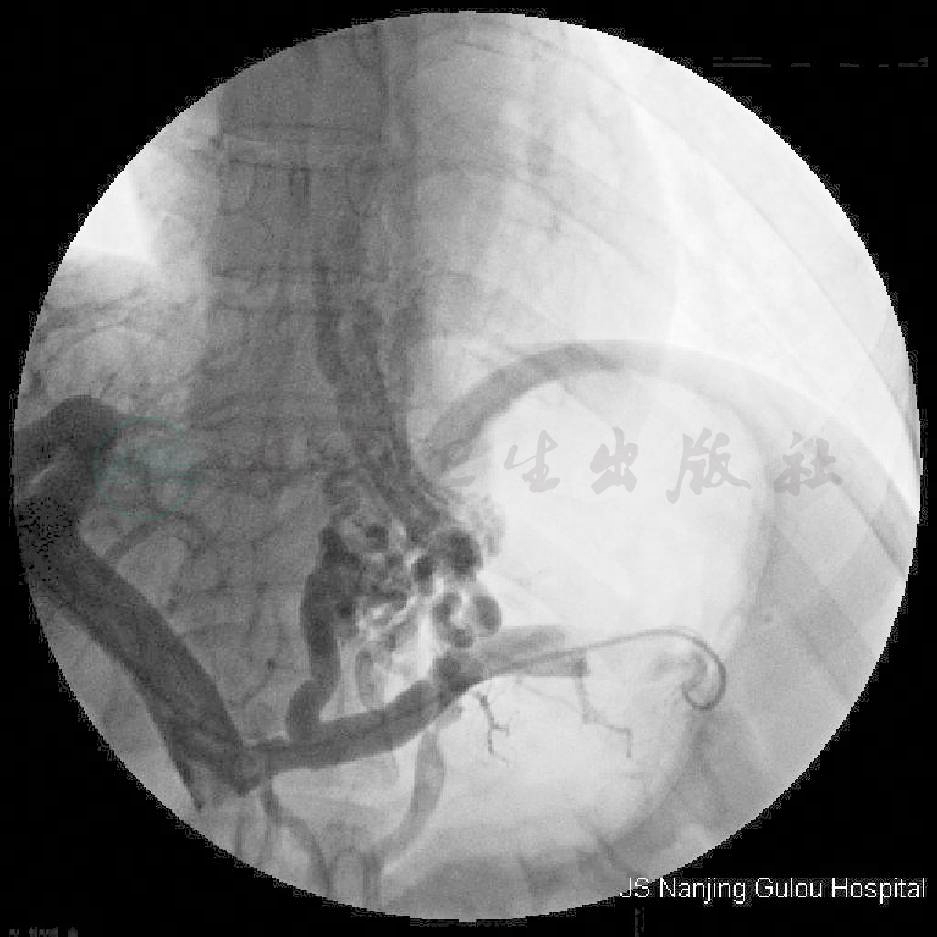

于出血当天行经皮经肝食管曲张静脉栓塞术,在B超引导下于腋中线第八肋间用PTC针经皮经肝穿刺门静脉成功,导丝超选入脾静脉,交换导管,脾静脉测压为41cmH2O,脾静脉造影见胃左静脉和胃后静脉增粗,分别向上形成食管胃底静脉丛,向下见胃肾分流(图1),COBRA导管分别超选入胃左静脉和胃后静脉(图2),共注入组织胶14ml,留药良好(图3),未见异位栓塞,再次行脾静脉测压47cmH2O,脾静脉造影见胃左静脉和胃后静脉完全栓塞(图4),拔除导管前用两枚钢圈封堵穿刺道(图5)。治疗后患者未再出血,5日后出院。

图6 第一次TIPS直接门静脉造影

常规颈内静脉穿刺,将RUPS-100穿刺系统经颈内静脉沿上腔静脉、右心房、下腔静脉插入肝静脉,冒烟观察肝静脉开口,于肝静脉与下腔静脉开口处2cm穿刺门静脉,拔出穿刺针,冒烟观察导管已进门静脉分叉处,沿导管将导丝置于肠系膜上静脉,RUPS-100穿刺系统沿导丝送入门静脉主干,交换造影导管,行直接脾静脉造影,门静脉测压为47.5cmH2O,用6cm×8mm梭形球囊扩张穿刺道,然后置入一个8cm×8mm的网状支架,再次行肠系膜上静脉造影,见置入支架后分流道畅通(图6,图7),门静脉测压29cmH2O,颈部拔管,穿刺处局部消毒、包扎。术后予以抗凝、抗血小板及预防性抗感染等治疗。